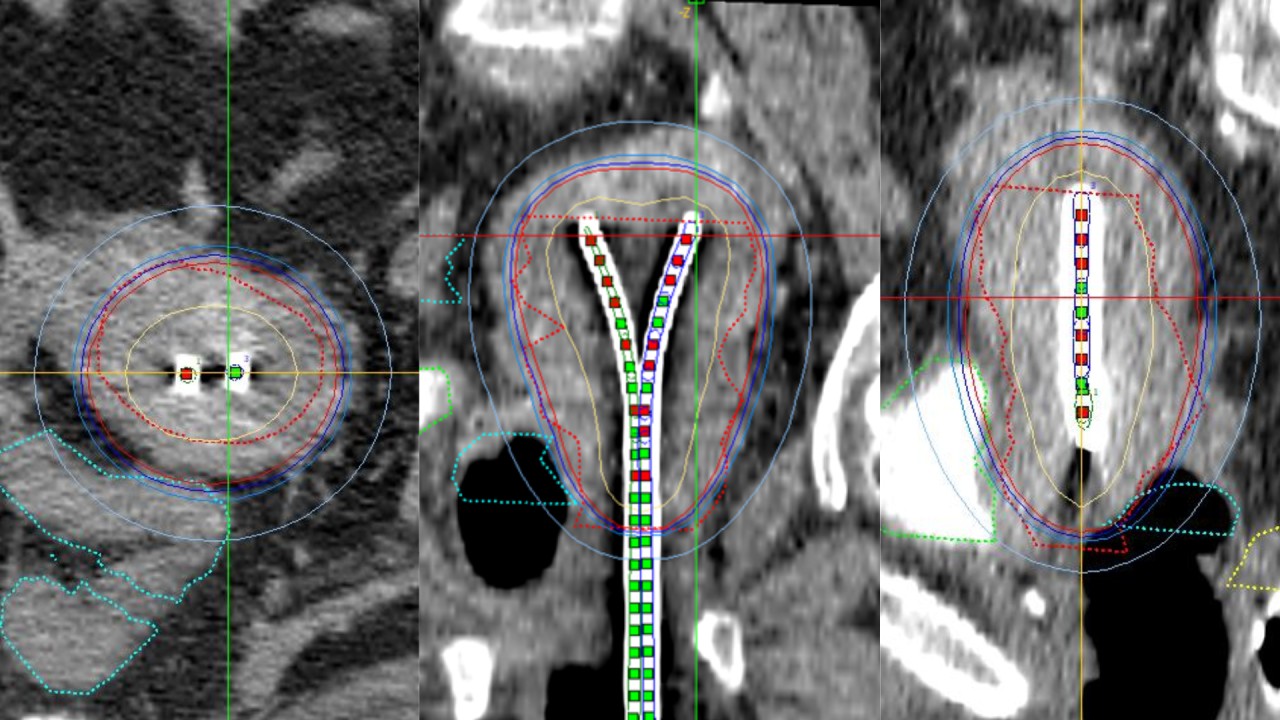

Երբ վիրահատությունը հնարավոր չէ․ բրախիթերապիան որպես արդյունավետ լուծում